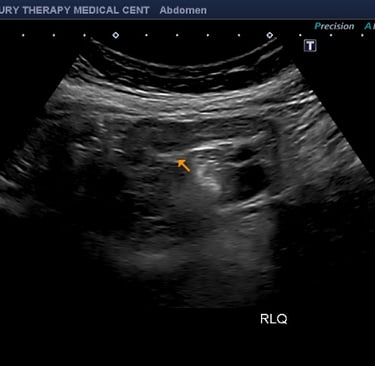

⭐ 2. Tecnología avanzada con imágenes de alta resolución

Contamos con equipos de ultrasonido modernos que ofrecen claridad superior en estructuras abdominales, facilitando diagnósticos más rápidos y exactos.